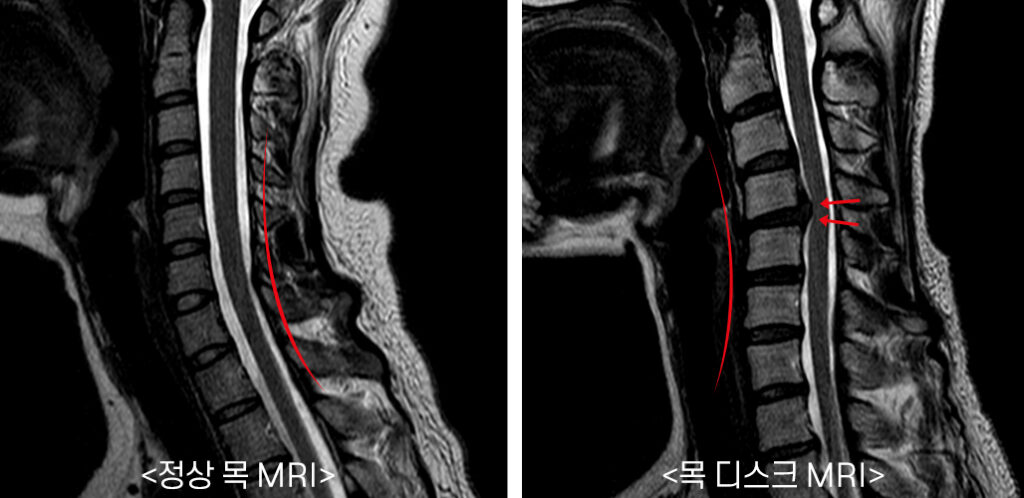

목 디스크는 목의 디스크(경추 디스크)에서 출현하는 질환으로, 경추 디스크 사이의 연골판이 터져 디스크 내부 물질이 경추 신경을 자극해 통증이나 저림증 등의 증상을 유발 해요. 목 디스크는 일상생활에서의 안 좋은 자세나 많은 운동, 부상 등이 이유가 되는 것이 될 수 있기도하고, 시간이 지날수록 발생 확률이 높아져요. 목 디스크의 증상으로는 목 부위의 통증, 팔의 저림, 근육 약화 등이 있으며, 증상이 난폭한 경우 수술 등의 치료가 필요할 수 있어요. 그리하나 대개의 경우 치료 없이도 시간이 지나면 증상이 호전되는 경우가 대부분입니다.

목디스크 증상 2. 목 자세

목디스크 증상 목 자세이고요. 현대인들은 스마트폰이나 모니터를 많이 사용하다보니 목이 앞쪽으로 당겨져있는 것처럼 자세를 많이 취하게 된다 하였습니다. 이런 자세는 정상적인 목뼈를 전환 시켜 여러분이 아시는 거묵목 증상이 나타나게 되는 이유가 되는 것입니다.